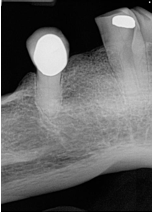

What is the problem with this Phalangioma X-ray?

May occur with digital sensors or film,Patient’s finger was positioned in front of the receptor during finger-holding method

How would you resolve this Phalangioma X-ray?

Never allow the patient to hold a receptor during exposure